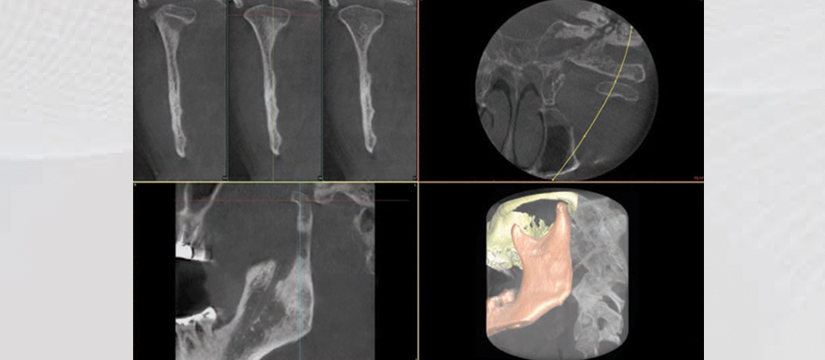

- TMJ Closed Mouth

- TMJ Open Mouth

- 3D TMJ Left Positioning

- 3D TMJ Right Positioning